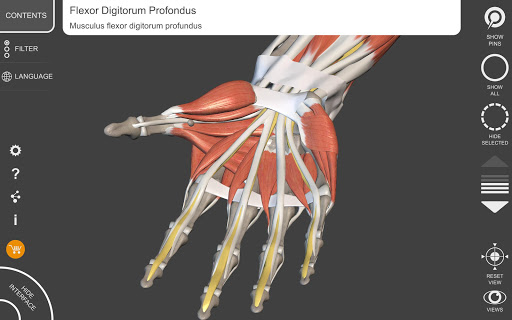

"Anatomía - Atlas 3D" permite estudiar la anatomía humana de forma fácil e interactiva.

A través de una interfaz sencilla e intuitiva es posible observar cada estructura anatómica desde cualquier ángulo.

Los modelos anatómicos 3D son especialmente detallados y con texturas de hasta una resolución de 4k.

La subdivisión por regiones y las vistas predefinidas facilitan la observación y el estudio de partes individuales o grupos de sistemas y las relaciones entre los diferentes órganos.

MODELOS ANATÓMICOS 3D

• Sistema musculoesquelético

nervioso • Sistema respiratorio • Sistema digestivo • Sistema urogenital (masculino y femenino) • Sistema endocrino • Sistema linfático • Sistema ocular y auditivo CARACTERÍSTICAS • Interfaz sencilla e intuitiva • Rotar y hacer zoom en cada modelo en el espacio 3D • Opción para ocultar o aislar uno o varios modelos seleccionados • Filtro para ocultar o mostrar cada sistema • Función de búsqueda para encontrar fácilmente cada parte anatómica • Función de marcador para guardar vistas personalizadas • Rotación inteligente que mueve el centro de rotación automáticamente • Función de transparencia • Visualización de músculos a través de niveles de capas desde las superficiales hasta las más profundas • Al seleccionar un modelo o un pin, aparece el término anatómico relacionado • Descripción de los músculos: origen, inserción, inervación y acción • Mostrar/ocultar interfaz de usuario (muy útil con pantallas pequeñas) MULTILINGÜE • Los términos anatómicos y la interfaz de usuario están disponibles en 11 idiomas: latín, inglés, francés, alemán, italiano, portugués, turco, ruso, español, Chino, japonés y coreano • Los términos anatómicos se pueden mostrar en dos idiomas simultáneamente REQUISITOS DEL SISTEMA • Android 8.0 o posterior, dispositivos con al menos 3 GB de RAM Reversi